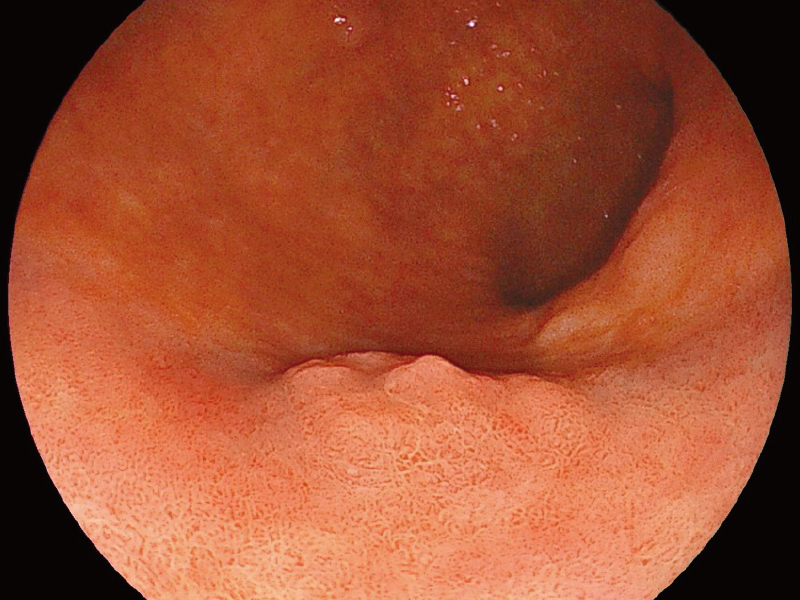

The 2mm close-up observation is expected to improve visibility during treatment.

*3

White Light Imaging

BLI (Blue Light Imaging)

*3 The images are not strictly close observation at 2 mm